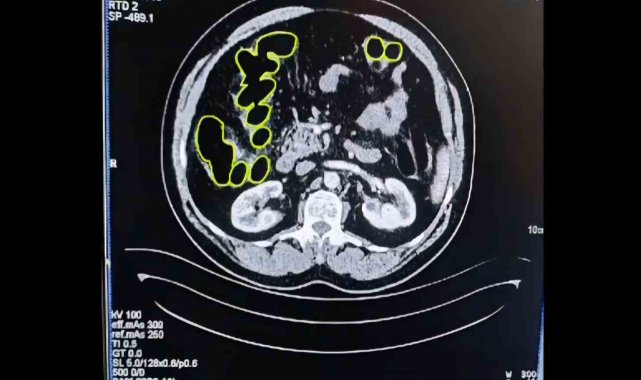

Şüphelilerin Kayseri Şehir Hastanesinde iç beden muayenesine alınırken, mide ve bağırsaklarında da çok miktarda kapsül şeklinde uyuşturucu olduğu değerlendirilen yabancı maddeler tespit edildi.